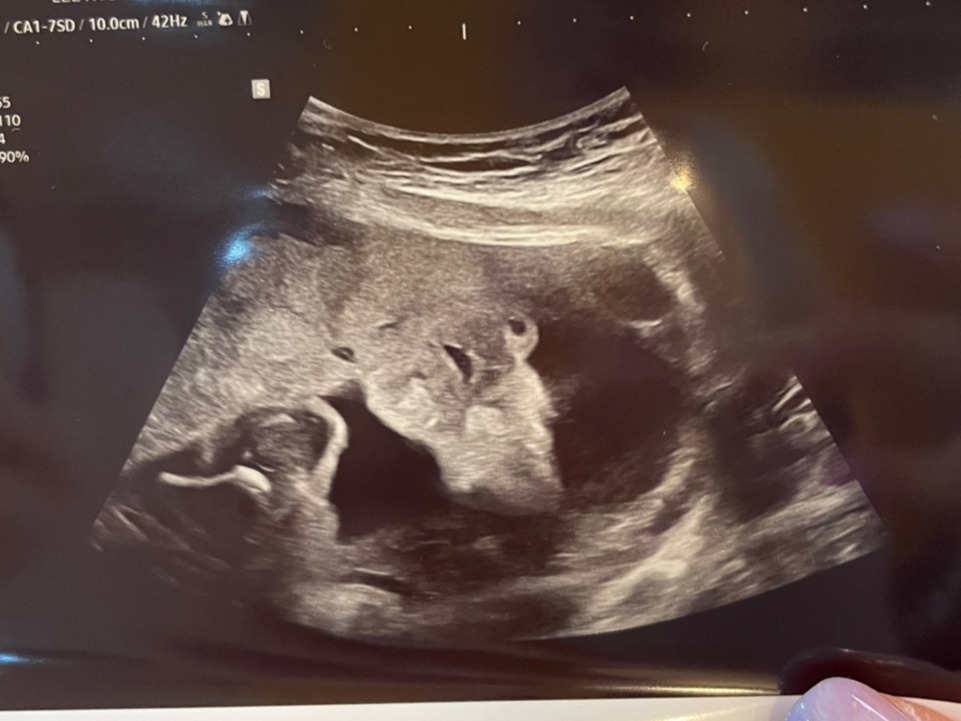

아기의 얼굴을 보려고 열심히 들여다보았는데, 아기가 태반에 얼굴을 파묻고 있어 얼굴을 제대로 보지 못했다. 여전히 아빠를 닮은 것 같은 코와 입이 잘 보였는데, 양수를 먹고 있는 건지 꼬물꼬물 거리는 입술이 너무 귀여웠다.

KakaoTalk_20221008_145038766_01.jpg 콧구멍과 입이 보이는 초음파 사진, 얼굴은 보여주지 않았다...